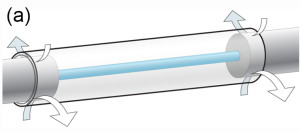

Surgery: (a) a scaffold diagram (arrows=sutures), (b) surgical pictures of the Mg insertion into nerve at surgery and (c) the PCL conduit in place.

Mg: magnesium; PCL: poly(caprolactone).2